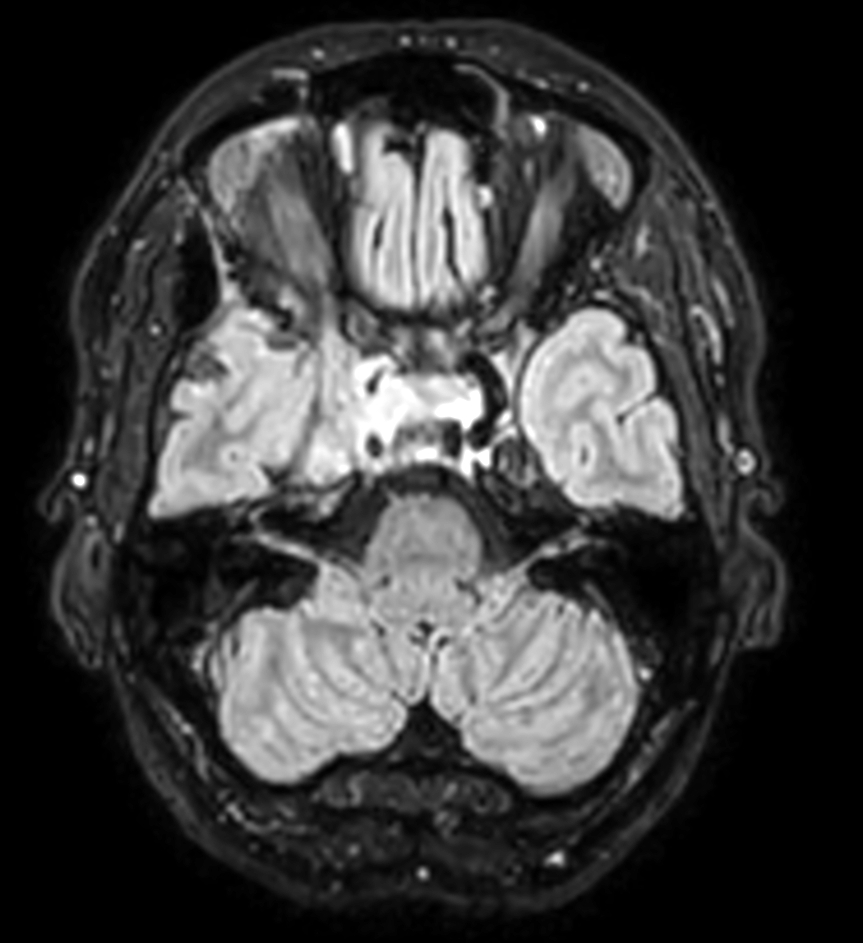

Young female referred for stereotactic treatment underwent MRI simulation.  Flex L Coils in combination with integrated FlexCoverage Posterior coil were used to image the patient in the stereotactic mask in Ingenia MR-RT 1.5T.

Axial 3D T1w TFE pre contrast